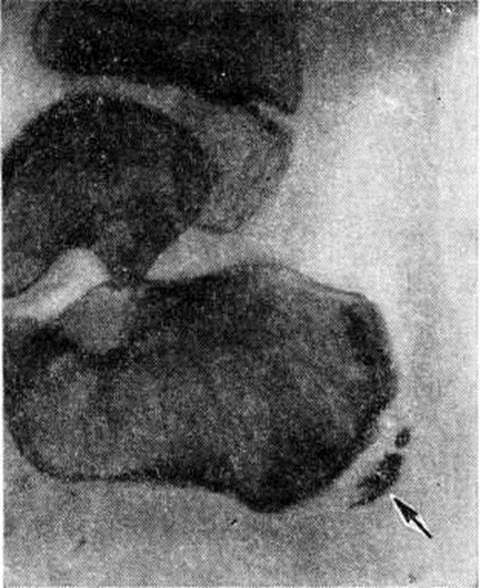

Хаглунда — Шинда болезньХаглунда — Шинда болезнь (P. S. Е. Haglund, шведский ортопед, 1870—1937; Н. В. Schinz; синонимы апофизит пяточной кости) — вариант остеохондропатии апофизов с локализацией патологического процесса в бугре пяточной кости. Впервые описана в 1907 год Хаглундом под названием перелом эпифизарных ядер пяточной кости, а в 1922 год Шинцем как апофизит пяточной кости. Встречается редко. Развивается чаще в возрасте 7— 15 лет. Поражение в основном одностороннее. Этиология окончательно не выяснена. Большинство исследователей считают, что остеохондропатия (смотри полный свод знаний) бугра пяточной кости является следствием многих патогенных факторов: микротравм, повышенной нагрузки (бег, прыжки), натяжения сухожилий мышц, прикрепляющихся к пяточному бугру (икроножной, подошвенной), эндокринных нарушений, сосудистых и нервно-трофических расстройств. Основной причиной, по-видимому, является хронический или острая травма в сочетании с местным нарушением кровообращения. В основе патогенеза Хаглунда — Шинда болезнь лежит остеодистрофия (смотри полный свод знаний) бугра пяточной кости. Начало заболевания обычно постепенное, но может быть и острое. Отмечаются жалобы на боли по задней поверхности пятки при ходьбе, при давлении задником обуви; иногда — на припухлость или отёчность этой области. Ограничена нагрузка на пятку, опора переносится на переднюю или передненаружную часть стопы, выражена хромота. При надавливании на бугор пяточной кости сзади отмечается боль, давление с боков пяточной кости и со стороны подошвы безболезненно. Сгибание и разгибание стопы может быть затруднено из-за болезненности в области бугра пяточной кости. Рентгенологическая диагностика основывается на следующих данных. В норме в бугре пяточной кости имеется несколько (3—4) ядер окостенения неправильной формы с неровными контурами, отделённых друг от друга светлыми прослойками хряща. При этом контуры бугра пяточной кости могут быть неровными, зазубренными, часто наблюдается асимметрия их оссификации. При Хаглунда — Шинда болезнь теряется гомогенность тени бугра пяточной кости, отмечается её пятнистость (секвестроподобная картина) из-за появления небольших округлых очагов резорбции с тонкими стенками и островков, состоящих из отложений минеральных солей. Возможно отделение краевых фрагментов, которые могут смещаться в сторону. Расстояние между пяточной костью и апофизом увеличивается из-за разрастания хряща (рисунок). Контуры костных поверхностей неровные. Нередко наблюдается интенсивная гомогенная минерализация бугра пяточной кости. Возможно образование на его месте двух-трёх фрагментов, не одинаковых по форме и содержанию минеральных солей. Дифференциальную диагностику проводят с туберкулёзным поражением пяточной кости, бурситом, периоститом, остеомиелитом, опухолевыми процессами. Лечение консервативное. В период обострения назначают покой (иммобилизация гипсовой лонгетой), физиотерапевтические процедуры, направленные на улучшение местного кровообращения. Вне периодов обострения рекомендуют режим, исключающий чрезмерную нагрузку на бугор пяточной кости (бег, прыжки), ношение ортопедической обуви с расширенным задником и углублением под пяткой (смотри полный свод знаний: Обувь, ортопедическая обувь). При резкой деформации заднего отдела пяточной кости возможно оперативное лечение: удаление выступающих костно-хрящевых разрастаний или клиновидная резекция пяточной кости в области бугра. При своевременно начатом и правильном лечении происходит полное восстановление структуры и формы пяточной кости. При позднем и нерациональном лечении бугор пяточной кости иногда остаётся увеличенным и деформированным, что особого влияния на функцию не оказывает, но затрудняет ношение обычной обуви. В таких случаях назначают ортопедическую обувь. |